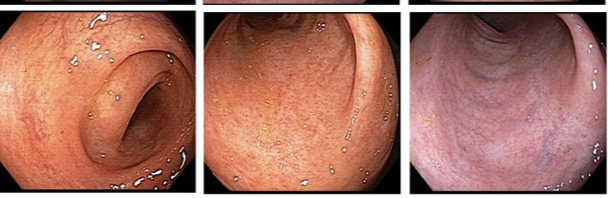

Q

Mayo score?

A

9